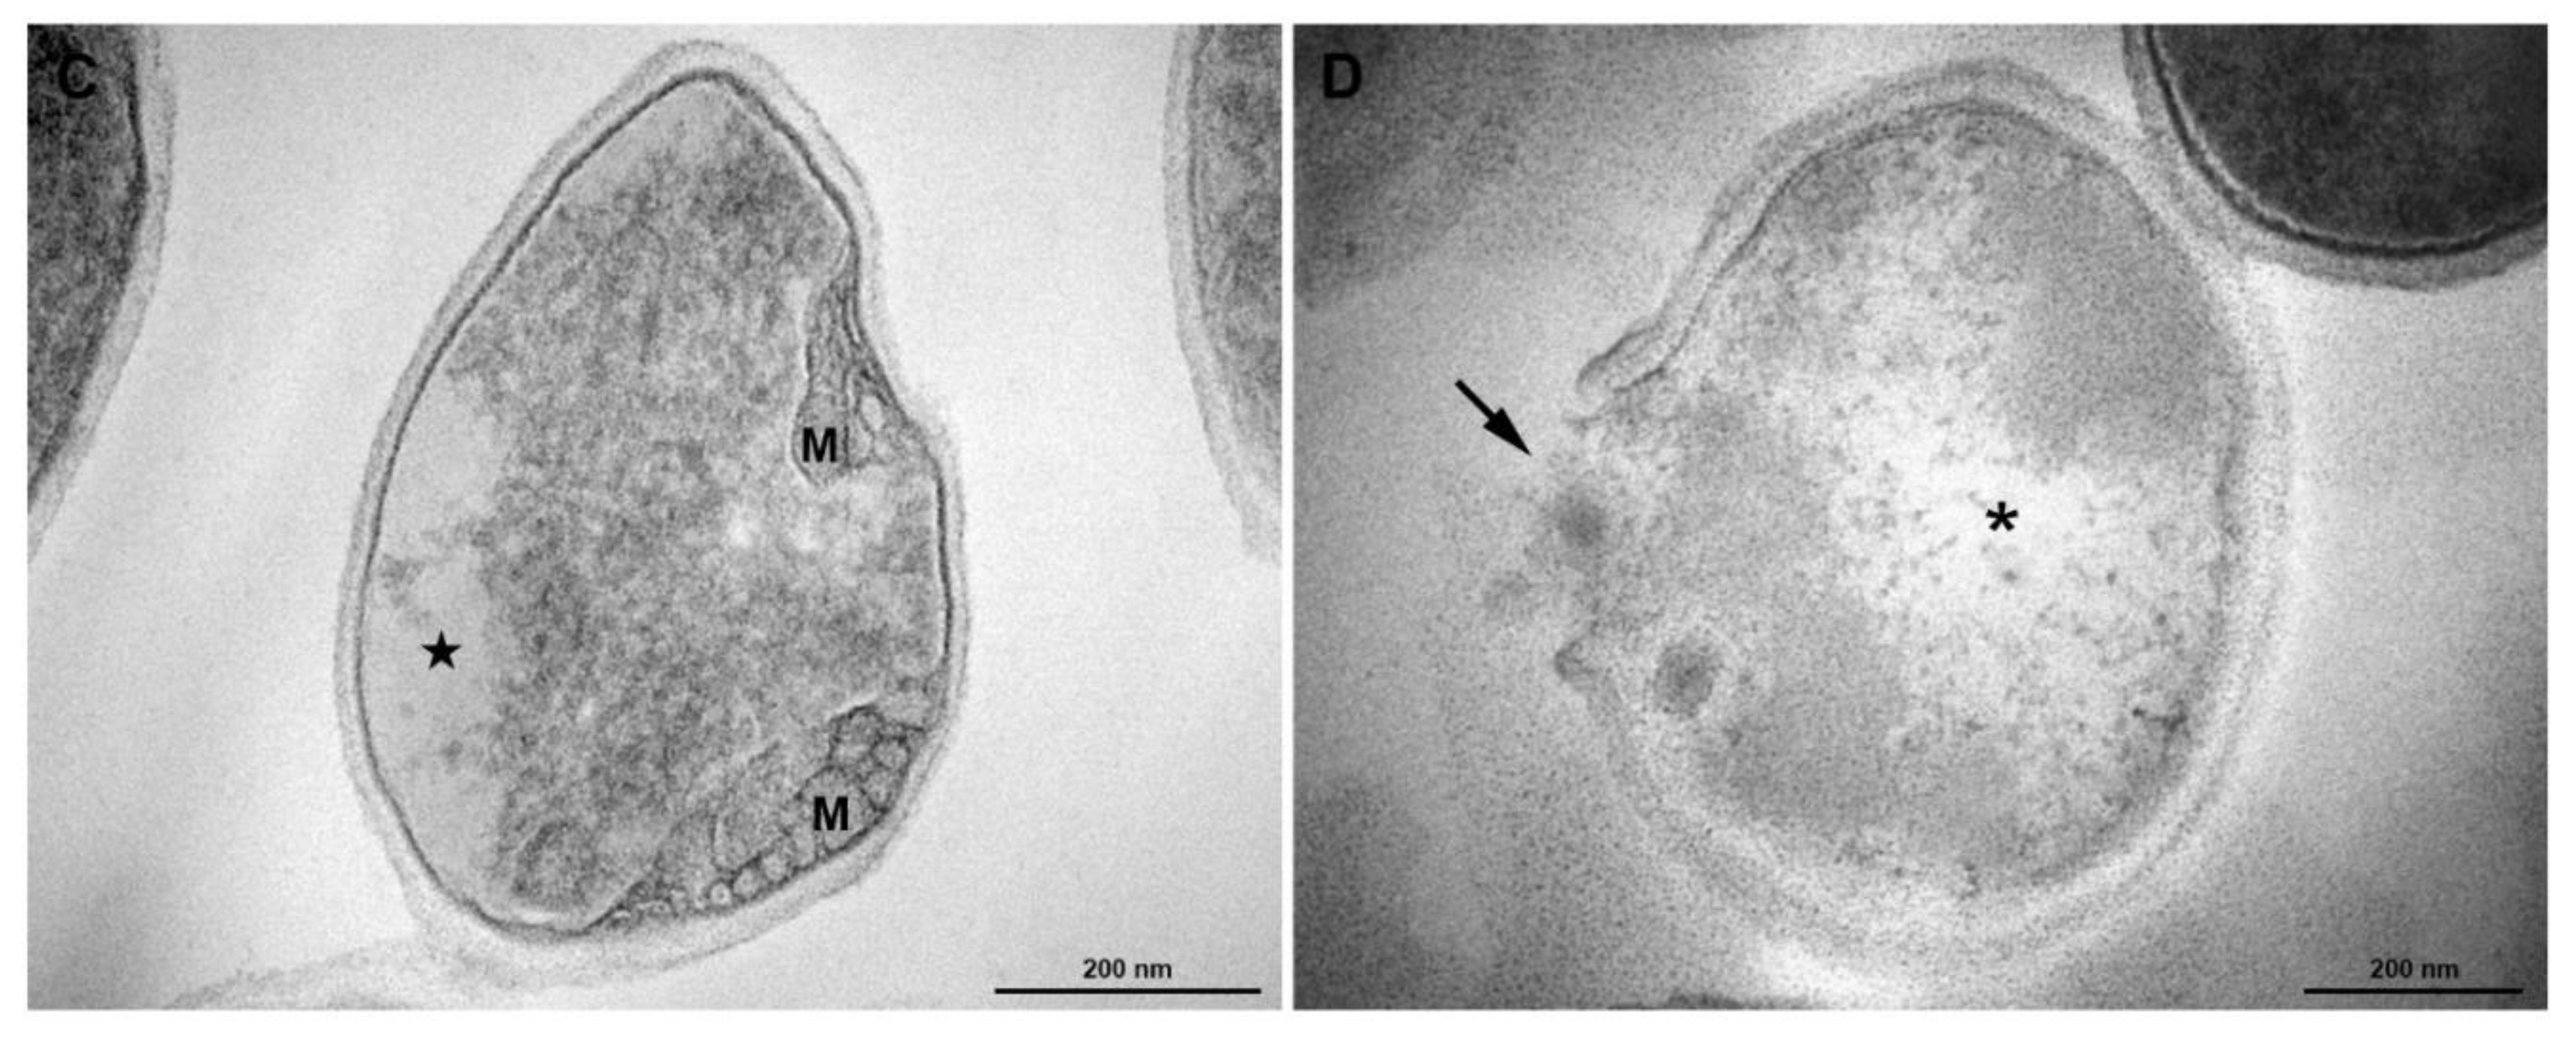

According to Figure 8, menadione treatment in association with antibiotic provoked severe morphological alterations in S. aureus. The cells showed abnormal electron density in the cytoplasm and cell wall with no visible tripartite-layers structure (Figure 8A,B). Changes in the shape and mesosome-like structures were also observed (Figure 8C). Cytoplasm disintegration and lysed cells were often seen (Figure 8D).

Figure 8.

Transmission electron microscopy of S. aureus treated with antibiotics (Menadione MIC/4) and Antibiotic CIM/4). (A) General view: some cells exhibit abnormal electron density in the cytoplasm (★) and altered cell wall with no visible tripartite-layers structure (black arrowheads). (B) Inset of Figure A. (C) Detailed view of a cell showing alterations in the shape, loss of cytosolic electron-density (★) and mesosome-like structures (M). (D) A lysed cell with cell wall disruption (arrow) and cytoplasmic disintegration (asterisk). Bars: A: 500 nm; B–D: 200 nm.